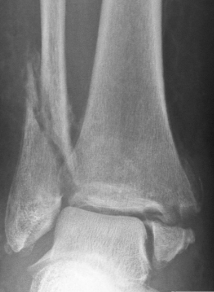

What type of fracture is this?

Pott

What is a pott fracture?

Complete fracture of distal fibula, may involve ligament damage and fracture of medial malleolus and distal tibia